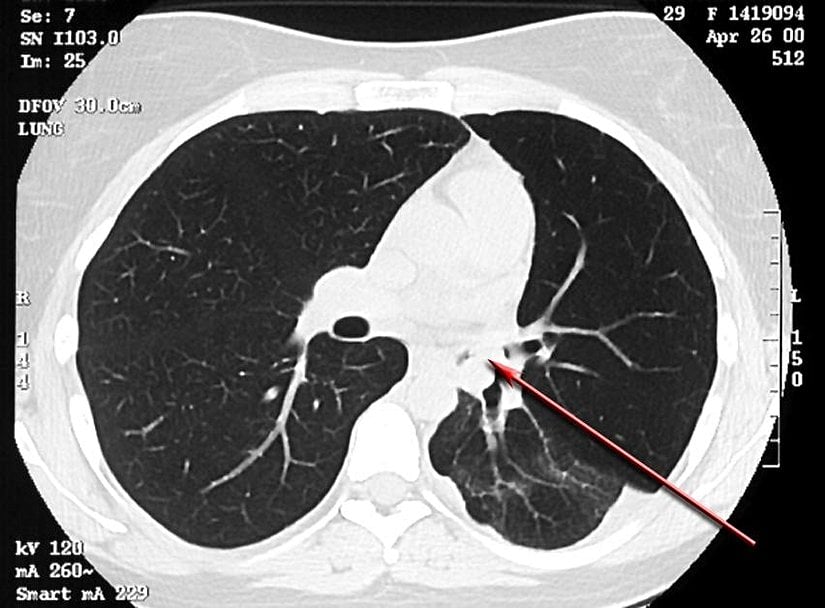

Çeşitli hava yolu tümörlerinin astıma benzer semptomlarla kendini gösterdiği rapor edilmiştir. Bu tümörler, aşağıdaki resimlerde gösterildiği gibi endobronşiyal karsinoid ve mukoepidermoid tümörleri içerir. Bir vakada, sol akciğerinde hiperlüsensi olan 14 yaşındaki bir erkek çocuğunun nihayetinde sol ana bronşta bronşiyal karsinoid olduğu bulundu.[119]

Diğer trakeal lezyonlar arasında bronkosentrik granülomatozis, subglottik stenoz, subglottik ağ, trakeal hamartom, bronkojenik kistler, leiomyoma ve trakeobronkopatia osteoplastika yer alabilir. Tüm bu trakeal lezyon tipleri astıma benzer semptomlarla rapor edilmiştir.